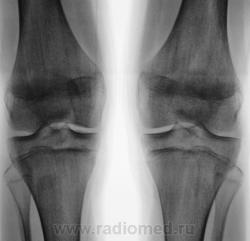

Женщина. 61 год. Вес 120 кг. Жалобы на боли и "хруст" в коленях. Рентгенологически - двусторонний артроз 3-й степени с наличием "вакуум-феноменов" в области внутренних менисков, большей выражености слева.

Сравнительная характеристика - в положении стоя наружные суставные щели гораздо шире, Х-образные конечности, ось нагрузки на внутренние отделы; в положении лежа уменьшаются. В положении лежа"соскальзывание" голеней наружу меньше. Внутренние суставные щели в положении лежа едва шире, очевидно сказывается резкое истончение мениска и хрящей со значительной потерей эластичности. Метрические показатели пока не оценивал. КАк поступить - мерить? тогда как лучше, дабы стандартизировать подход?